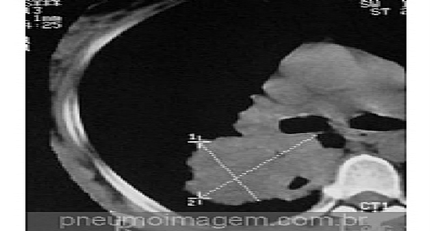

Veja imagens de pneumonias clicando aqui.